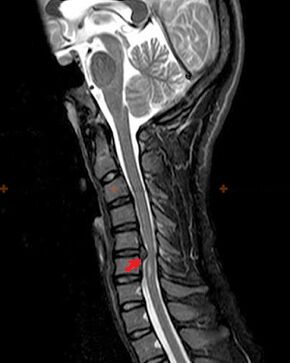

Osteochondrose ist eine radiologische Diagnose, da ein detailliertes klinisches Bild nur zum Zeitpunkt der Exazerbation vorliegt, während Veränderungen in der Wirbelsäule bei völligem subjektivem Wohlbefinden einer Person auftreten können. Ohne Röntgenuntersuchung kann nur von einem Verdacht auf Osteochondrose gesprochen werden, da ähnliche Symptome auch durch andere Erkrankungen (Myositis, Wirbeltumoren und andere) verursacht werden können.

Zur Diagnose einer Osteochondrose werden folgende Untersuchungsmethoden eingesetzt: Radiographie (vorzugsweise mit Funktionstests), MSCT und MRT. Die letztgenannte Studie ist vorzuziehen, da sie eine sehr klare Darstellung des Zustands der Zwischenwirbelstrukturen ermöglicht.

Zu den röntgenologischen Anzeichen einer Osteochondrose zählen die folgenden Veränderungen an der Wirbelsäule:

- Reduzierte Höhe der Bandscheiben.

- Vorhandensein marginaler knöcherner Wucherungen.

- Verletzung der Position der Wirbel relativ zueinander.

- Verformungen der Körper und Wirbelbögen usw.

Das Vorliegen der oben beschriebenen Veränderungen sowie durch MSCT und MRT festgestellte Veränderungen in der Struktur der Bandscheibe dienen als zuverlässige Anzeichen für das Vorliegen einer Osteochondrose.